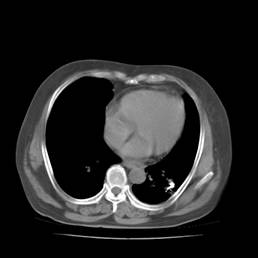

典型病例3:患者赵XX,男,76岁,住院号:493297,因咳嗽、咳痰、右侧胸痛1月余入院。于2015年5月29日胸部增强CT示:右肺上叶4.1cmx3.4cm占位。5月31日行CT引导下右肺穿刺活检术;6月1日活检病理证实:右肺上叶腺癌;6月16日行CT引导下右肺125I粒子植入治疗。7月22日患者复查胸部CT,原发病灶基本消失、粒子聚集。

术前CT片: